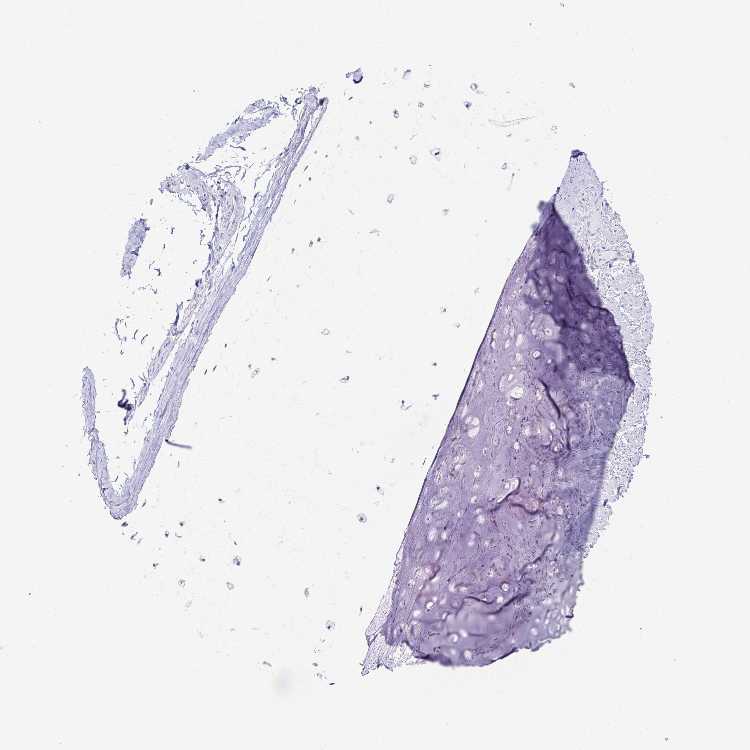

PRKCG